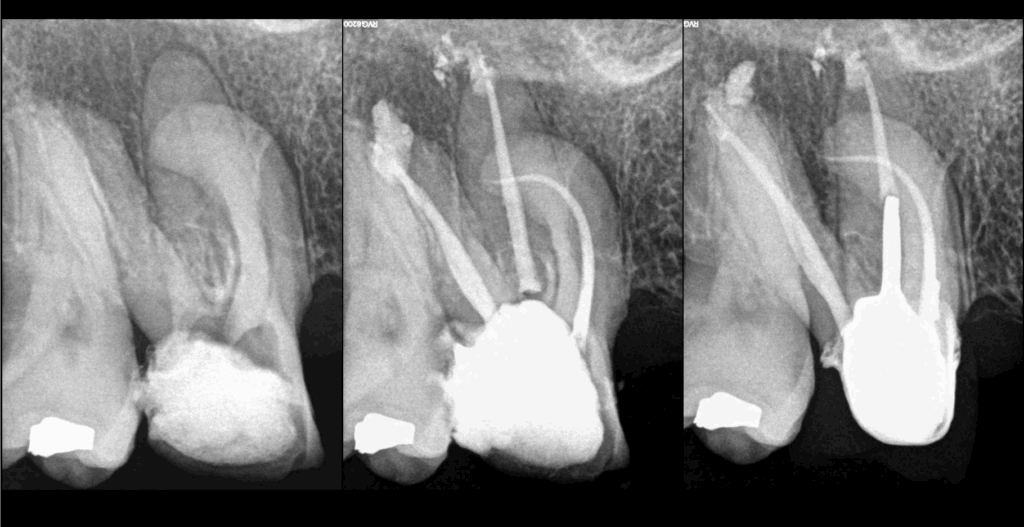

🔍 Pulpe précédemment traitée

📍Parodontite apicale asymptomatique

➡️ Indication de retraitement canalaire